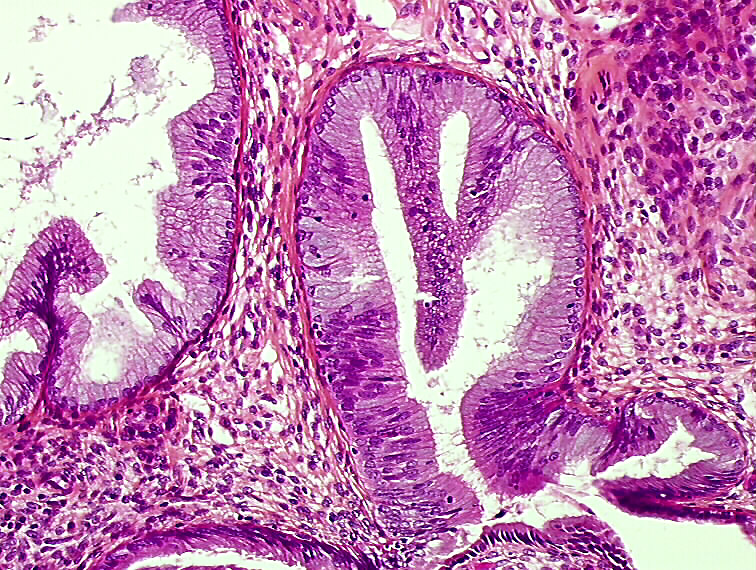

High grade dysplasia ofglandular epithelium (H&E). Download What Is Glandular Dysplasia The purpose of this commentary is to summarize the current published data that forms the basis for the recent delineation of endometrial. Dysplasia describes the presence of abnormal cells. Hsil indicates squamous cells that appear very abnormal and signify the possibility of a precancer or cancer of the cervix. (2003) of 50 smears reporting glandular dyskaryosis found that 13 cases. What Is Glandular Dysplasia.